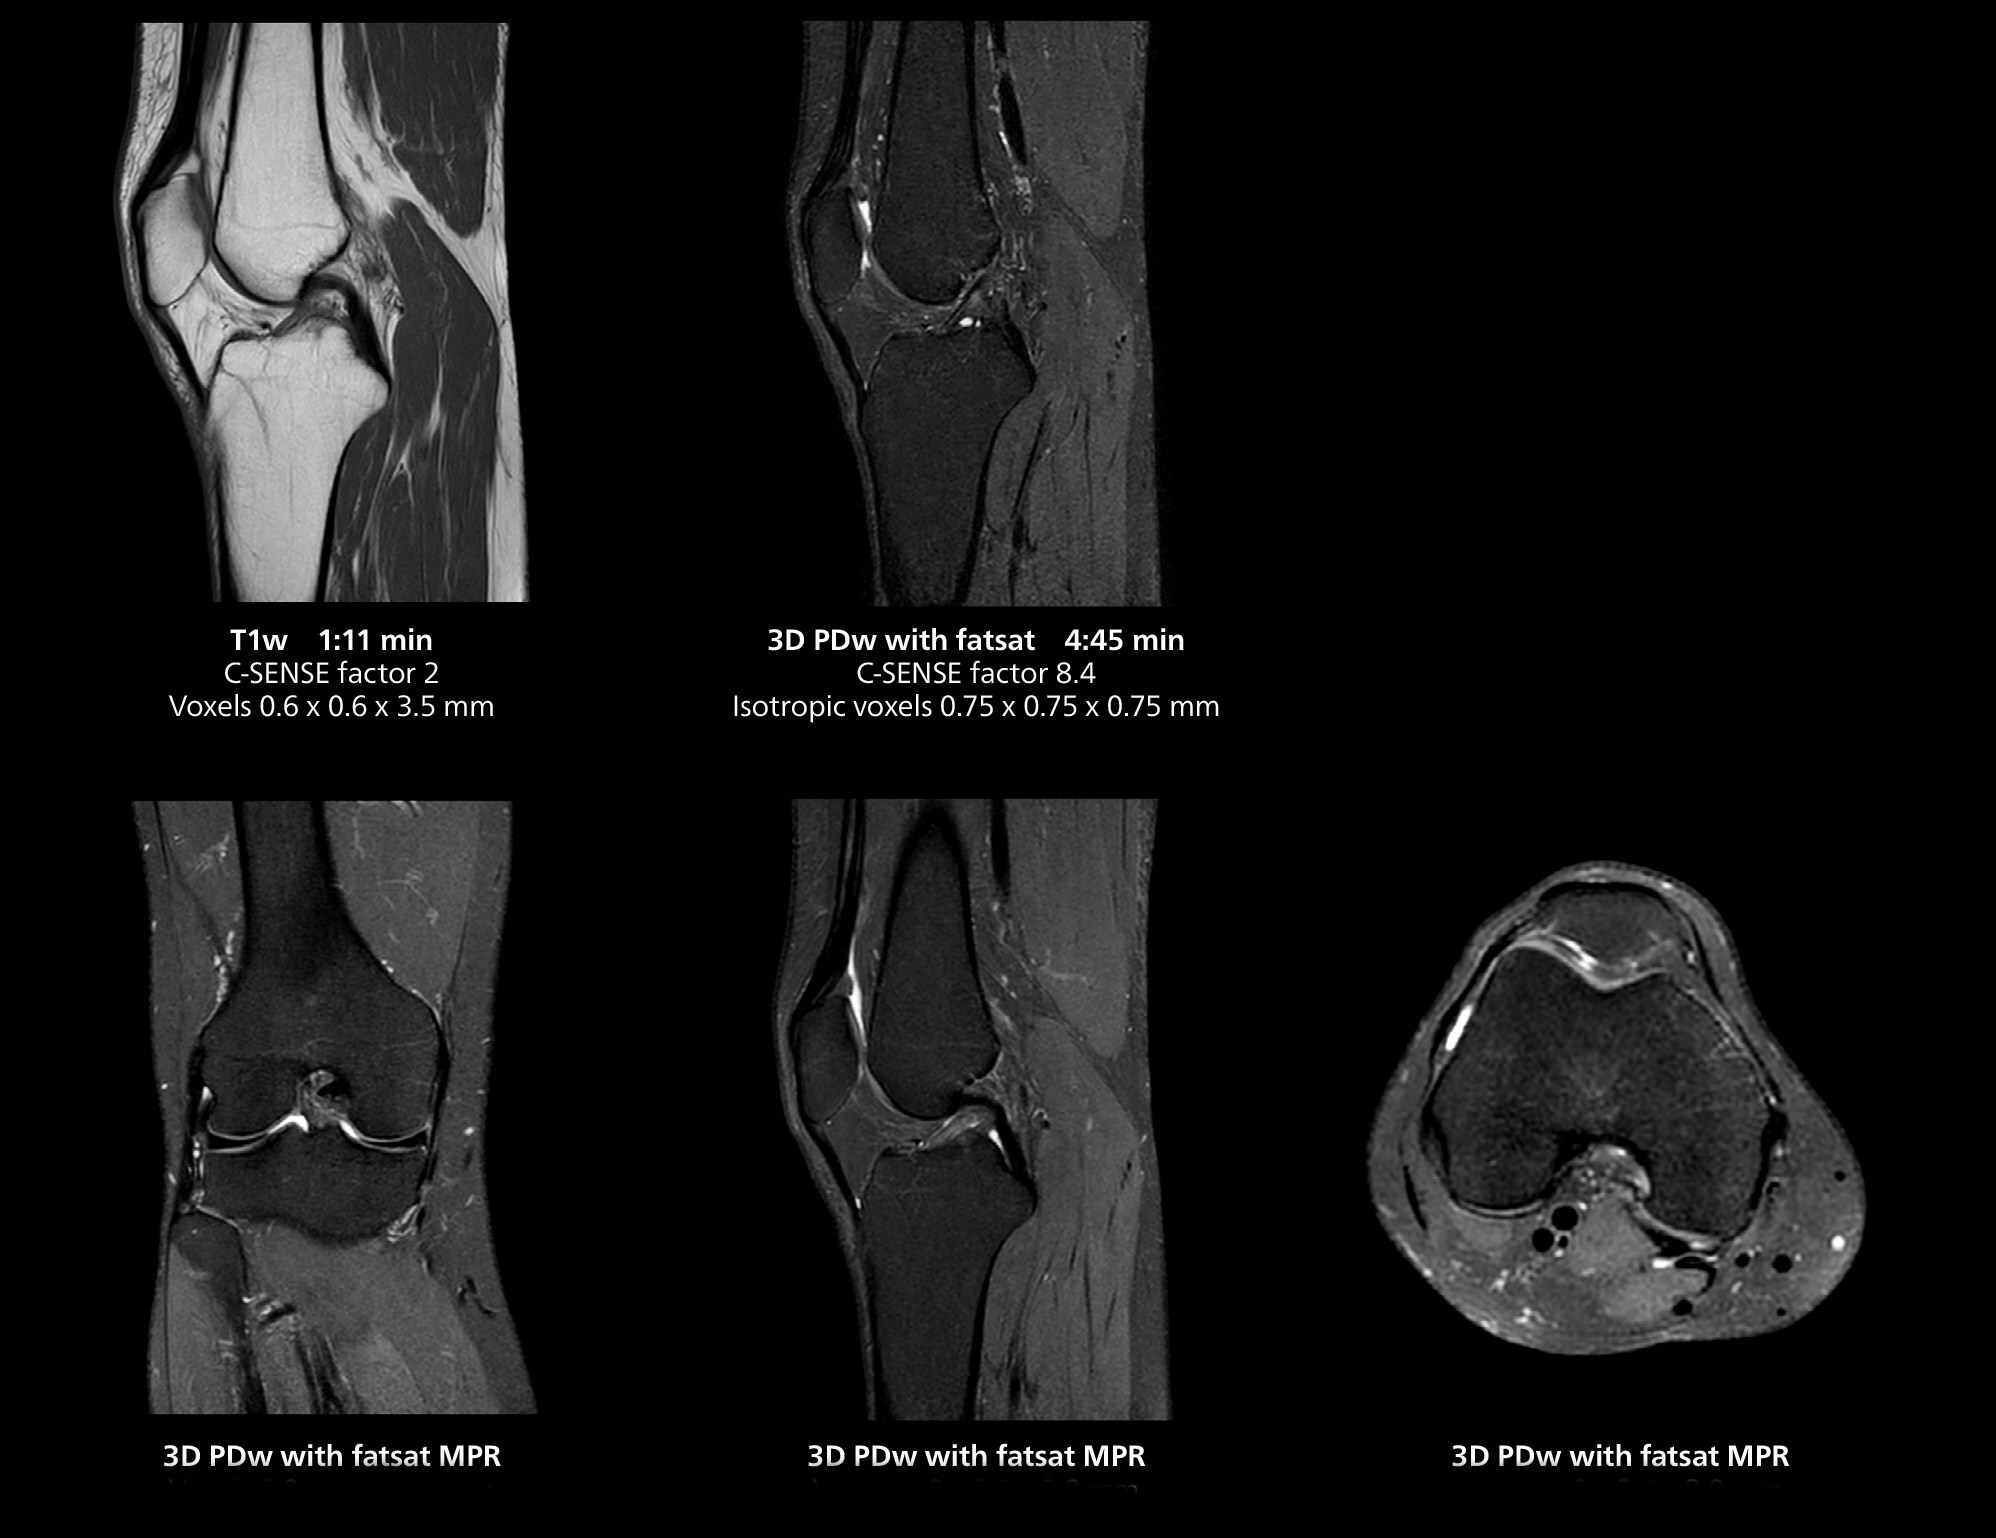

3D knee imaging. The isotropic high resolution 3D sequence in this MRI case allows for reformatting to obtain other orientations with high quality. Acquired on the MR5300 system.

According to Dr. Gellée, the hospital conducts an average of four studies each hour, totaling about 40-45 patients per day on their MR 5300. Studies are read by approximately 50 radiologists in the Bordeaux area. Dr. Gellée is especially satisfied with the image quality of the MR system. "I obtain higher image contrast and more anatomical precision than I was used to,” she says. “When I am able to choose, I request that studies be done on this system, because I get better anatomical image quality. For example, in the knees, I can get great images of the meniscus. To me, it looks as pretty as 3T.”

“We have more speed in 3D sequences,” Dr. Gellée states. “With Compressed SENSE, we can replace two or three 2D scans with one high-quality 3D scan. High-quality additional orientations are then obtained by post-processing of the 3D data set, thus saving scanning time.”